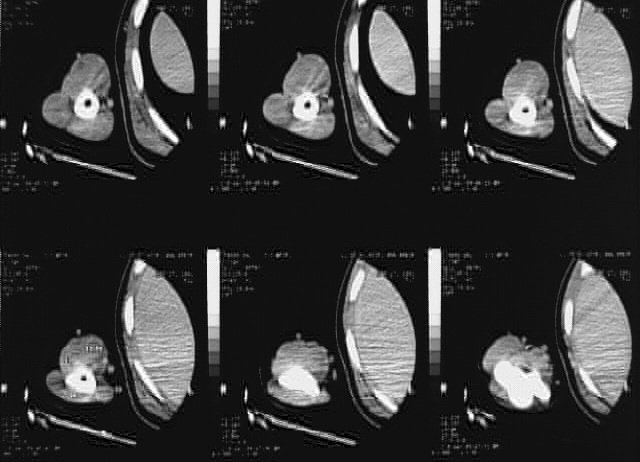

Upper Limbs:Right Arm CT:

No labels.